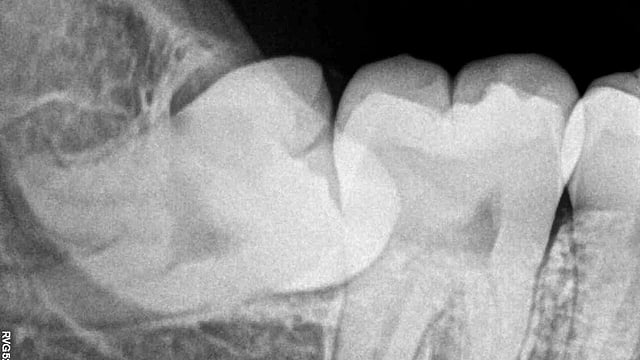

The tooth you threw away could have healed you: how wisdom teeth stem cells are emerging as a powerful tool. Nizil Shah, CC BY-SA 4.0, via Wikimedia Commons

Every tooth has a living center called pulp, a soft inner tissue filled with tiny blood vessels, nerves, and a very special type of cell, stem cells, the body's original builders.